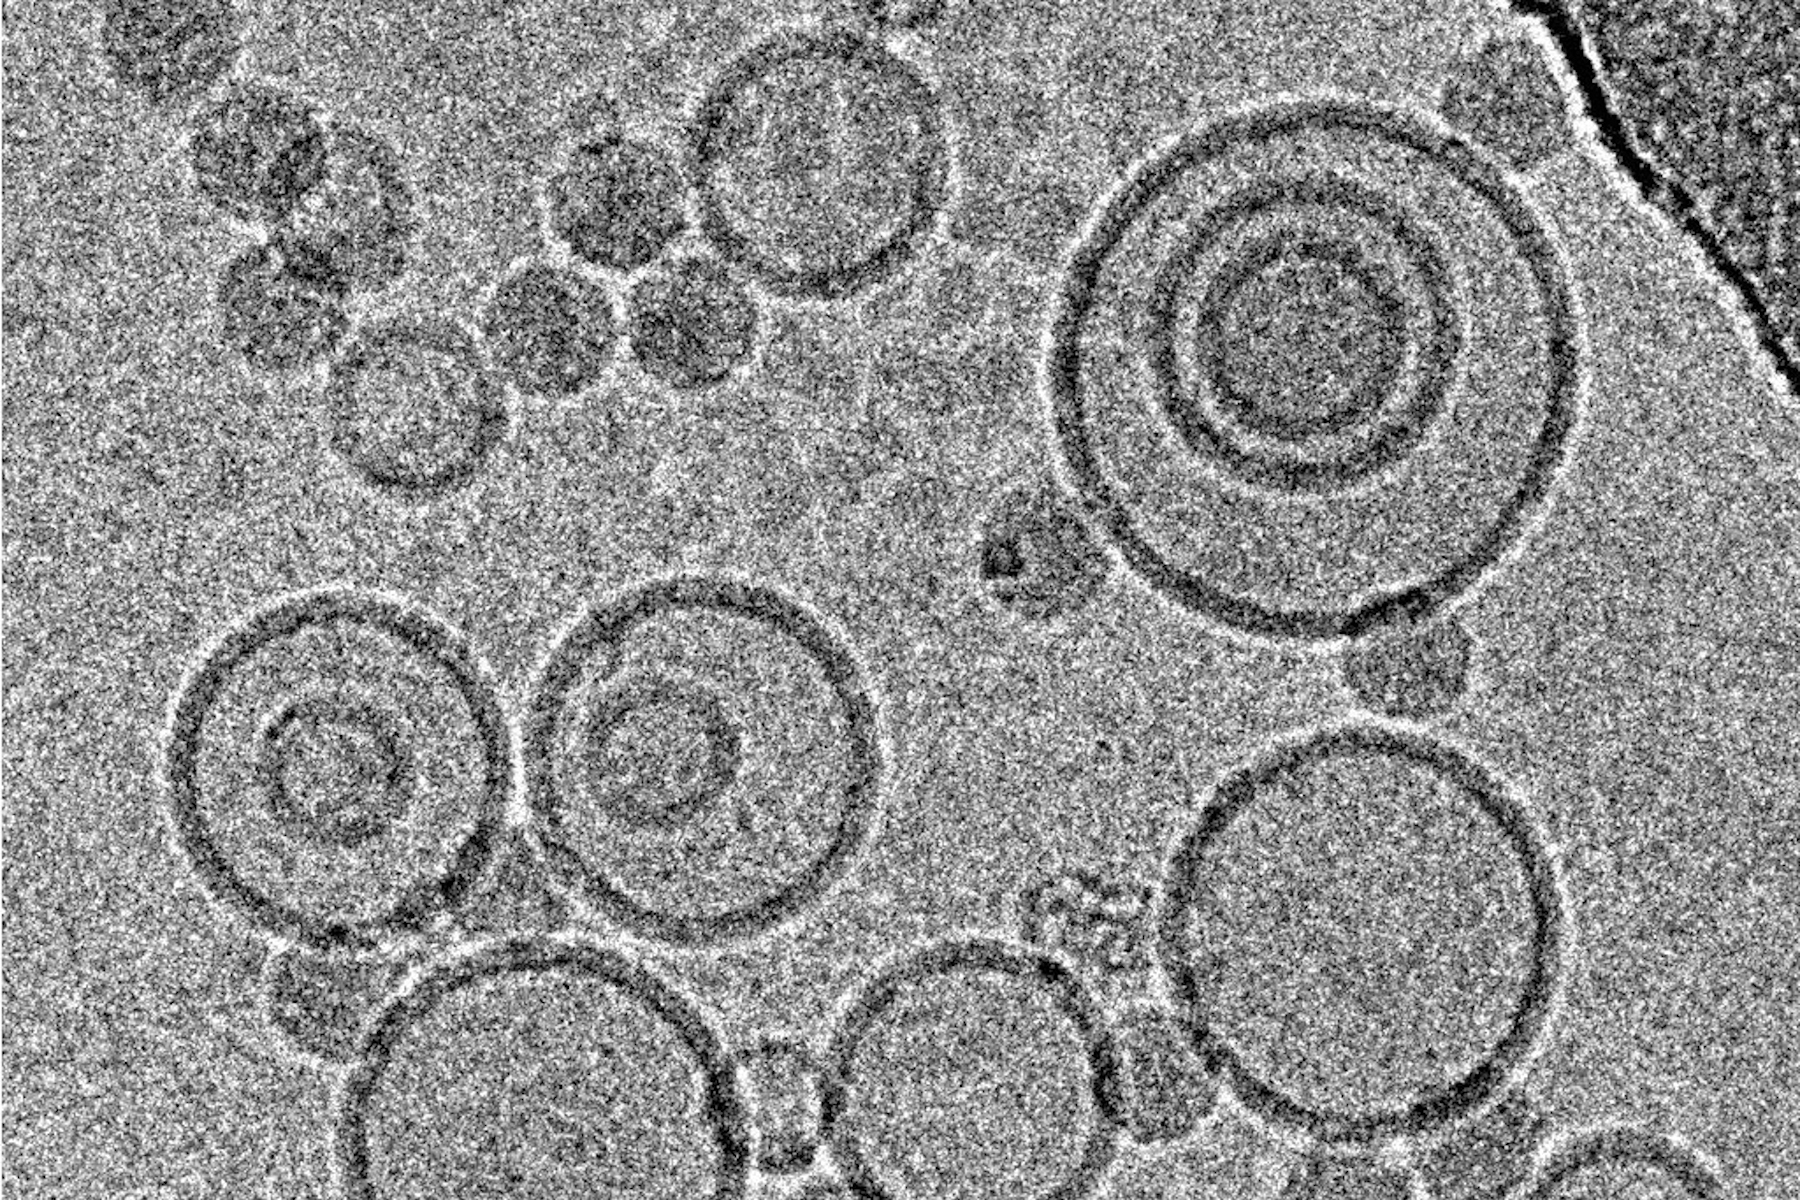

这些实验的样品使用徕卡EM GP冷冻,仪器在室温和95%rH的环境室中运行。从一系列预测试中获得每个标本在双蒸水中的最佳稀释度,以产生密度良好的标本,确保各个结构之间没有太多重叠。将4µl标本覆盖到涂有穿孔碳膜的辉光放电处理后的400目EM载网上。经过沉降后,根据使用的配方,对悬浮液吸液1.25-4.0秒。使用标准Whatman 1号滤纸和仪器的吸液传感器,吸液后立即将样品投入态乙烷中。

虽然来自冷冻TEM的尺寸信息与从动态光散射获得的数据互补,但结构信息是冷冻TEM独有的数据,并且各个标本之间呈现出的巨大差异,包括从球形液滴到扁平的片状结构(图5)。请注意此处显示的显微照片中没有污染,这是因为GP中集成了快速处理和一些防污染措施:这包括负压环境和初级冷冻剂中强大的“TF”蒸发器,它会产生干燥的低温氮气环境,以保护标本免受升温和污染。